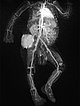

In coronal plane T1-weighted, fat-suppressed MRI after contrast administration, the tumor accumulates contrast strongly. The combination of the clinical picture with vascular, reddish-blue tumor immediately after birth, Kasabach-Merritt phenomenon and typical imaging suggests that the diagnosis of kaposiform hemangioendothelioma is very likely.